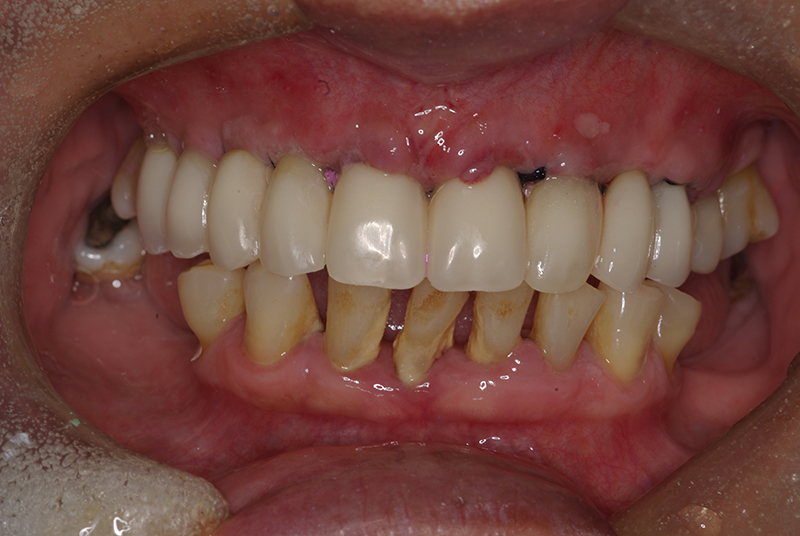

A Carga Imediata é uma técnica odontológica avançada que permite a colocação de uma prótese dentária fixa logo após a cirurgia de instalação dos implantes ou em poucos dias. Isso elimina a espera tradicional de meses para a integração completa do implante ao osso, oferecendo uma solução rápida e segura para restaurar dentes perdidos.

Embora seja uma solução moderna, nem todos os pacientes são candidatos ideais para a Carga Imediata. O sucesso do tratamento depende de fatores como:

- Quantidade e qualidade do osso disponível.

- Ausência de infecções ou doenças periodontais ativas.

- Condições gerais de saúde que favoreçam a cicatrização.